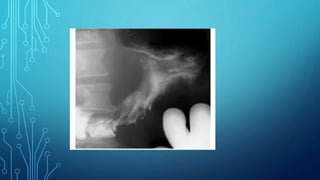

Radiography. This is atechnique of X-ray examination, in which a static image of an object is obtained, recorded on any information carrier: X-ray film, photographic film, digital detector. Any anatomical area can be captured on radiographs. Pictures of the entire anatomical region (head, chest, abdomen) are called overview. Pictures showing a small part of the anatomical area are called sighting pictures.

Some organs areclearly visible in the images due to natural contrast (lungs, bones), others (stomach, intestines) are clearly visible on radiographs only after artificial contrast. Passing through the object of study, X- rays are delayed. Where the radiation is delayed more, shading areas are formed. Where there is less - enlightenment.

X-ray images canbe positive and negative. In a negative image, bones appear light, air appears dark, and in a positive image, vice versa.